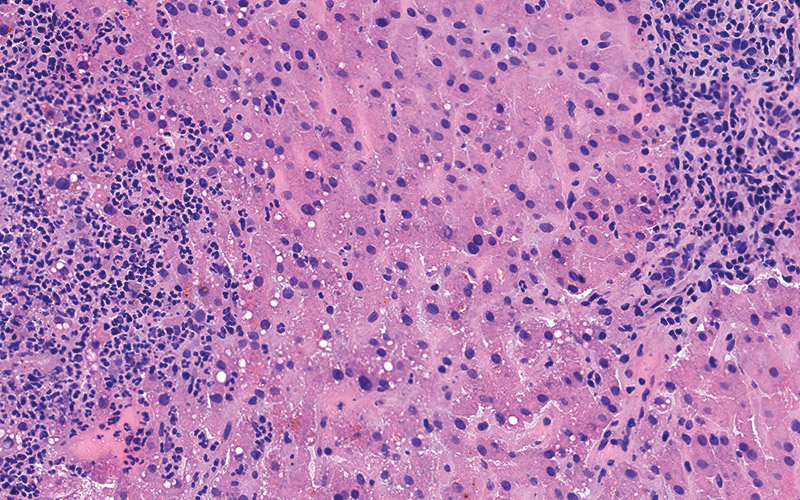

High Quality Results

Pathologists rely heavily on the frozen section technique for intra-operative consultation when the surgeon requires a rapid diagnosis or immediate feedback regarding surgical margins. Frozen sections offer a short turnaround time (15-20 minutes) but usually have the disadvantage of lower diagnostic quality than paraffin sections due to cryoembedding artifacts and variability in staining protocols.

Milestone offers a new approach to overcome these limitations by combining the artifact-free freezing process of PrestoCHILL with the superior processing and staining capabilities of PRESTO PRO.

The advantage of PRESTO PRO is that it provides a standardized and reproducible process that is capable of both efficient processing and staining protocols. This results in improved morphology of the analyzed specimens and maintains a high standard of result quality.